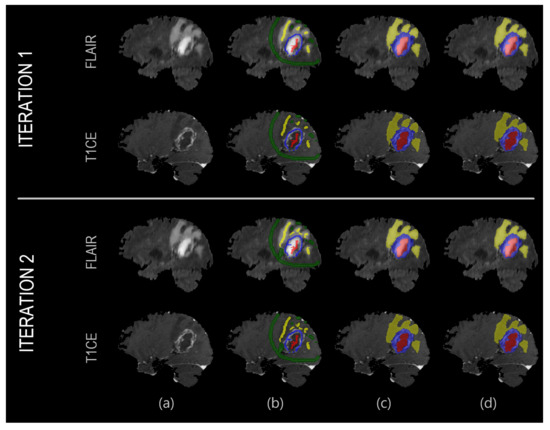

2.2. Proposed Segmentation Algorithm